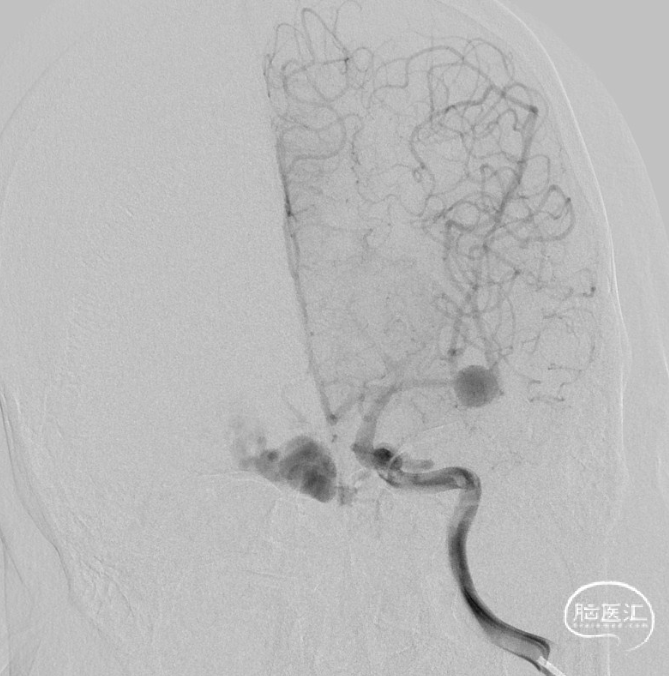

一期治疗

治疗经过

二期治疗